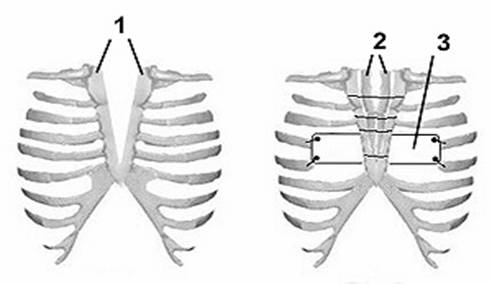

Рис. 9. Схема коррекции ВРГ по методике клиники.

1. – расщепленная грудина, 2. – реберные аутотрансплантаты, 3. – пластина.